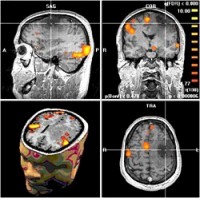

Primjena MRI u neurologiji

Magnetna rezonanca je najpreciznija metoda za dijagnostikovanje bolesti

mozga, kao na primjer: vaskularnih oboljenja (šlog,

krvarenje), ekspanzivnih procesa, (dobroćudnih i zloćudnih tumora), demijelinizacionih

oboljenja (multipla skleroza),

epilepsije, itd.